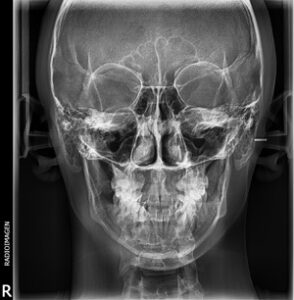

Radiografía frontal de cráneo, también de gran utilidad en ortodoncia y cirugías maxilofaciales.